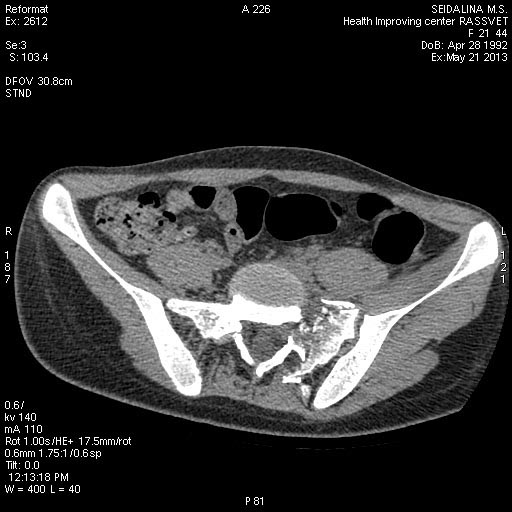

КТ до операции.